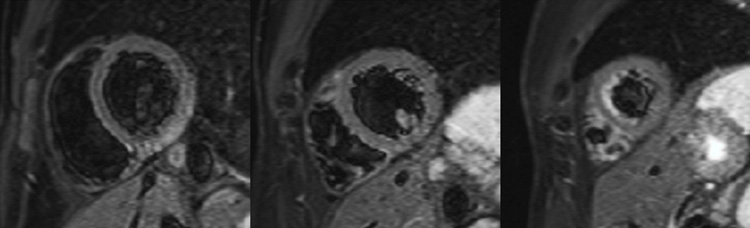

Figure 5 : Séquence cartographie T2 - Coupes petit-axe basal (A), médian (B) et apical (C)

Présence d’une zone d’œdème myocardique inféro-latéro-basale avec une élévation importante du T2 mapping à 65 ms (norme < 50 ms), a fortiori bien supérieure à la valeur de T2 mapping du reste du myocarde, mesurée à 45 ms.

Astuce quant à l'analyse du T2 mapping

La séquence de T2 mapping permet de détecter la présence d’œdème myocardique selon deux méthodes possibles en pratique :

- une zone avec une valeur de T2 mapping myocardique ≥ 50-55 ms (norme < 50 ms).

- une zone avec une valeur de T2 mapping élevée comparativement à une zone myocardique saine.

Attention : l’œdème myocardique n’est pas spécifique de myocardite aiguë, mais peut aussi être présent pour un infarctus du myocarde, un syndrome de Takso-tsubo, une sarcoïdose, ou n’importe quelle maladie de système en poussée…